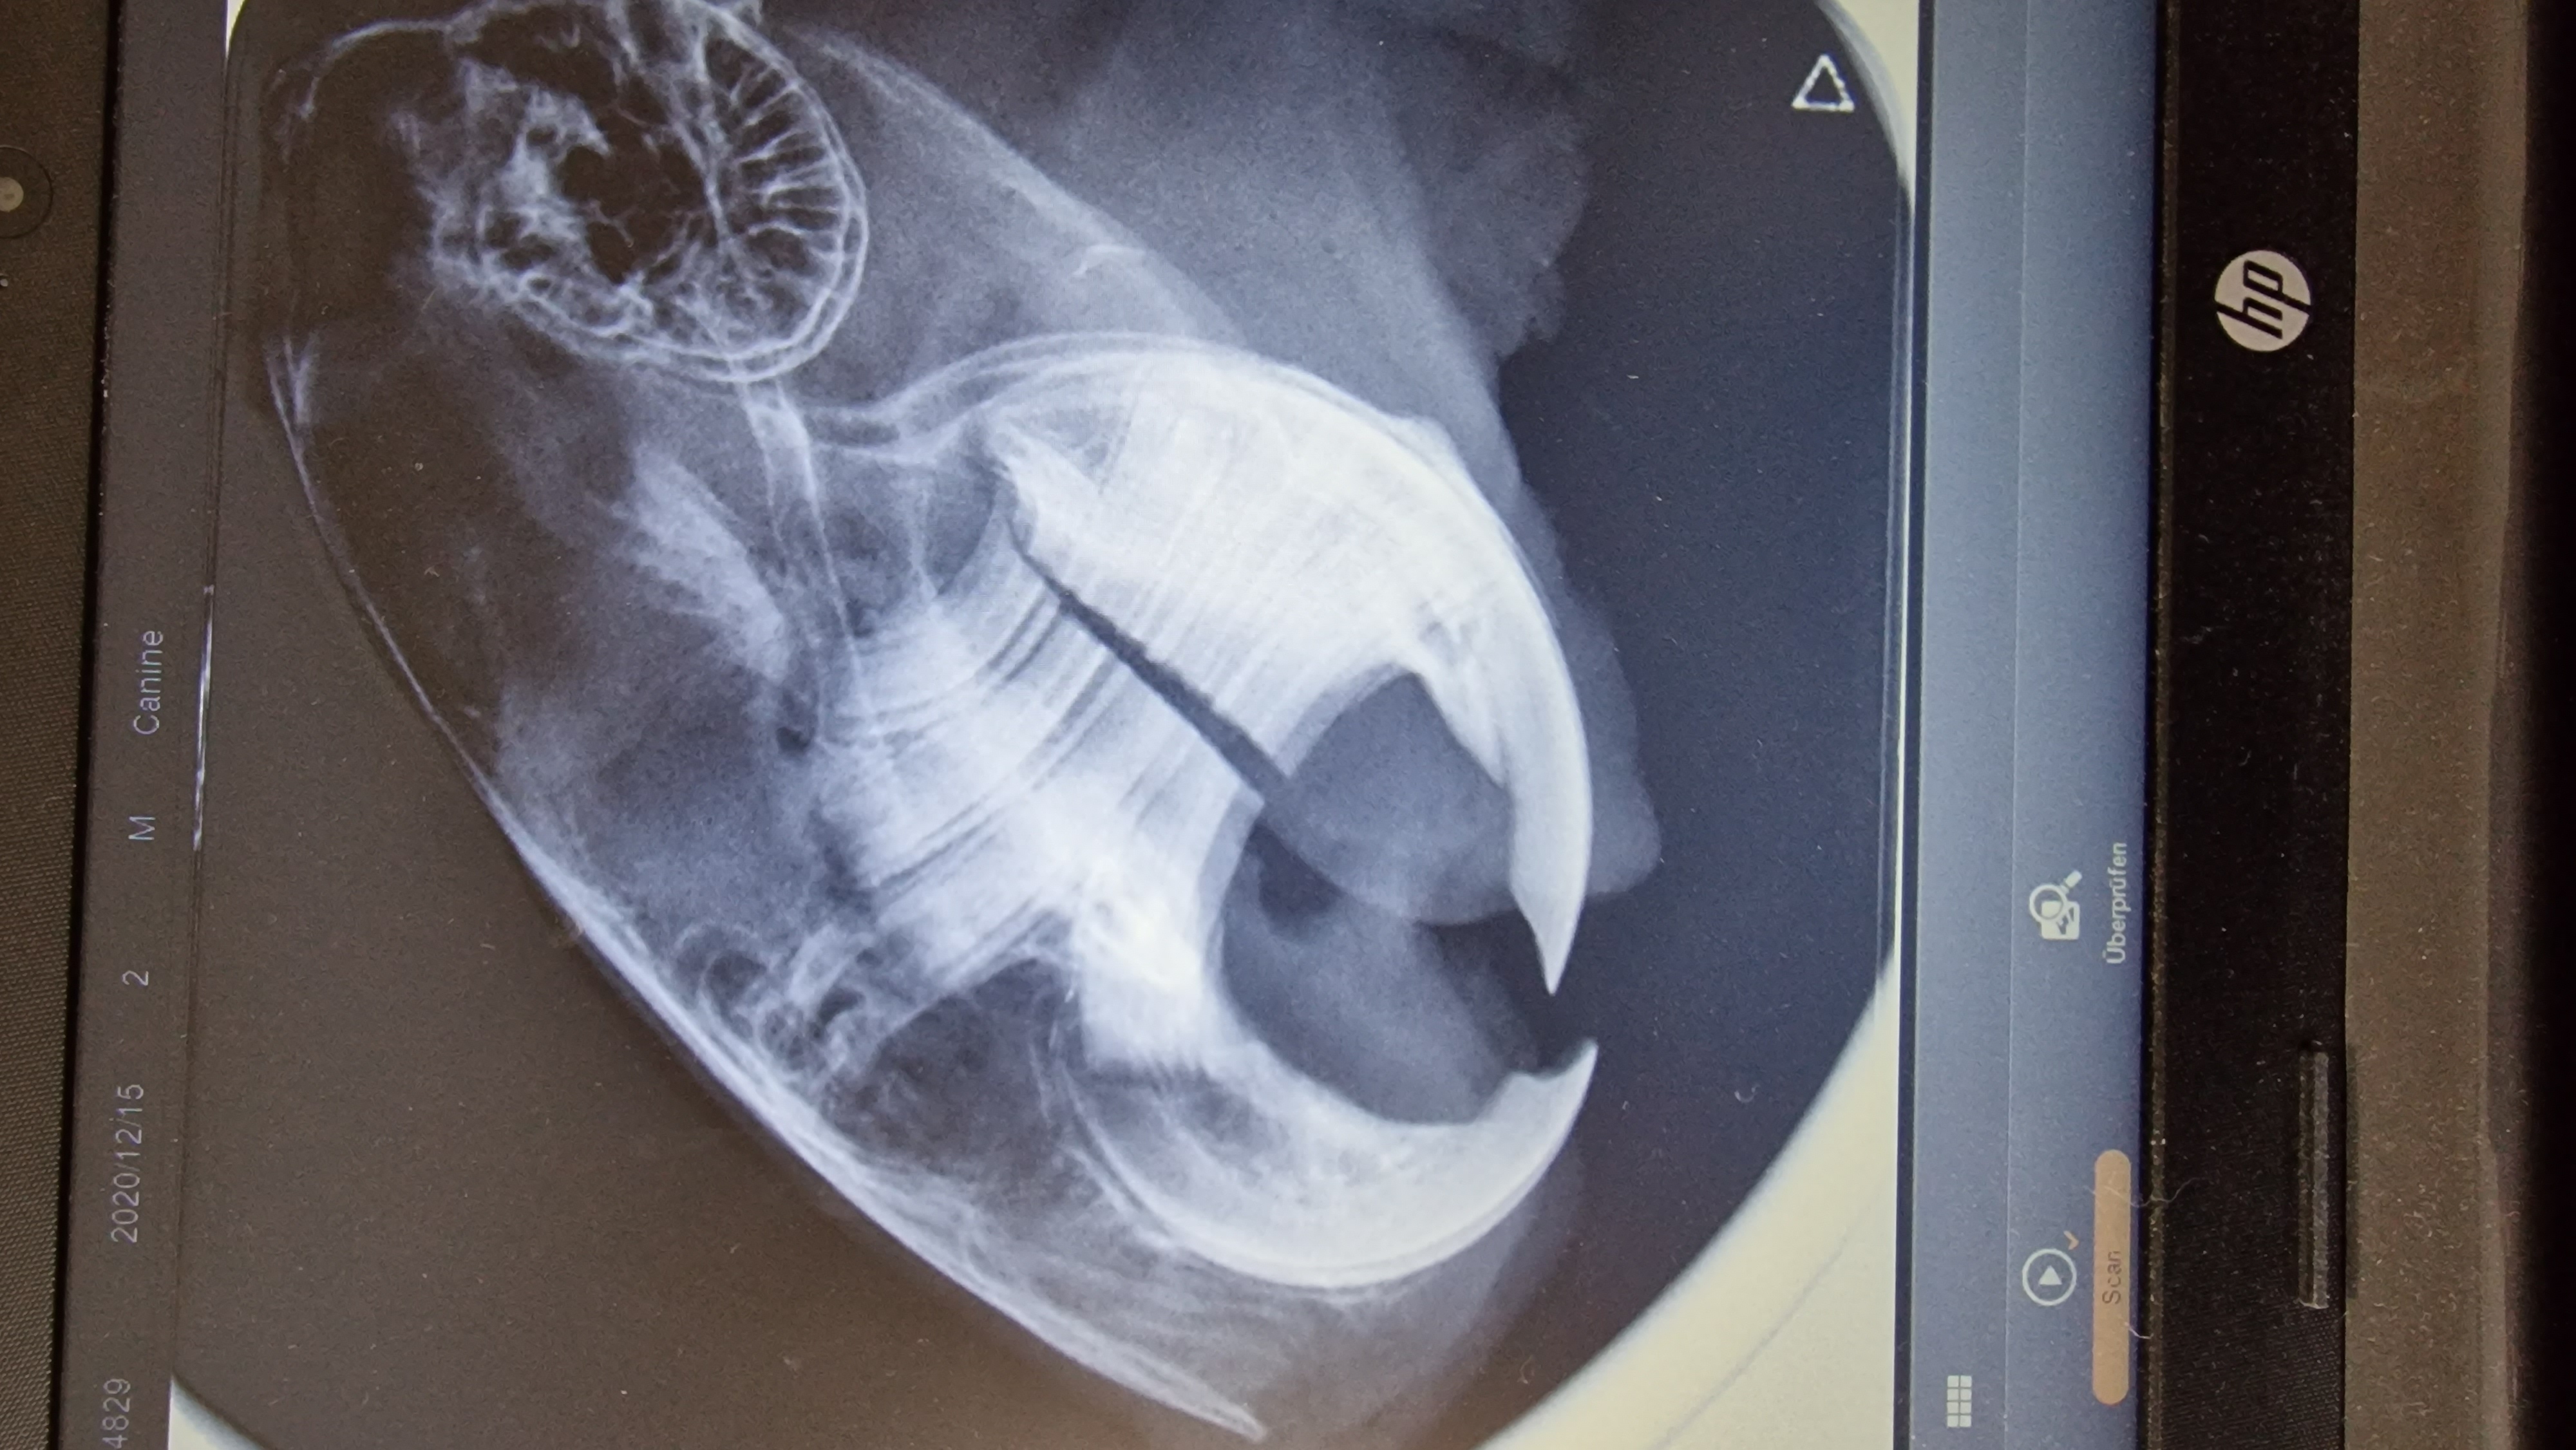

Wir waren heute beim röntgen, nachdem ein Degu immer mal wieder Niesanfälle hat.

PS: die Zähne sehen tatsächlich wirklich gut aus. Nur unten könnte man mit etwas Fantasie eine Exostosevermuten, aber das können auch die sich überlagernden Ebenen sein.

Der Degu hat immer mal wieder Niesanfälle, Antibiotika, Schleimlöser und Entzündungshemmer hatte nichts gebracht.. Nun wurde noch eine Probe entnommen. Am Freitag weiß ich mehr.Octodon hat geschrieben: 24. Okt 2023, 18:48 Ursache für was denn?